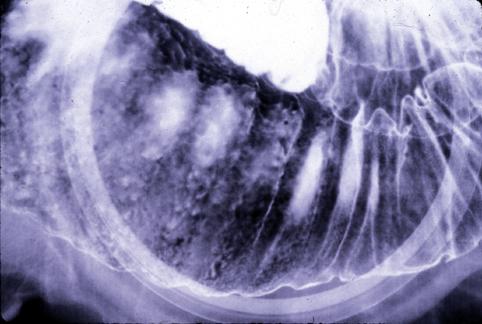

확실한 벽의 비후를 동반한 원발성의 B형 소장 악성 림프종(국립암센터 히가시병원<세키구치 류조>와 큐슈암센터의 공동작성

[Image-ID:5426]

질환(병리주체)의 분류

악성 림프계종양/악성 림프종

부위(장기별)

소장/공장

검사방법

X-P

종양의 최대경(밀리미터)

40이상

종양의 심달도

s(a)